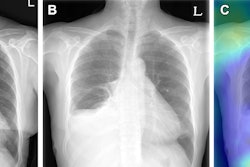

Integration of AI for chest x-rays on PACS. (a) The AI result attached to the second image of the original chest x-ray contains a contour map, abbreviations, and the abnormality score of detected lesions. Doctors can simply refer to the AI results by scrolling down the original image on the PACS. (b) The highest abnormality score is used as the total abnormality score of each image, and this was listed as a separate column (red square) on the PACS. Image and caption courtesy of npj Digital Medicine through CC BY 4.0.The investigators compared reading times according to the presence of lesions detected by AI for any one of the following eight abnormalities: atelectasis, cardiomegaly, consolidation, fibrosis, nodule, pleural effusion, pneumoperitoneum, or pneumothorax.